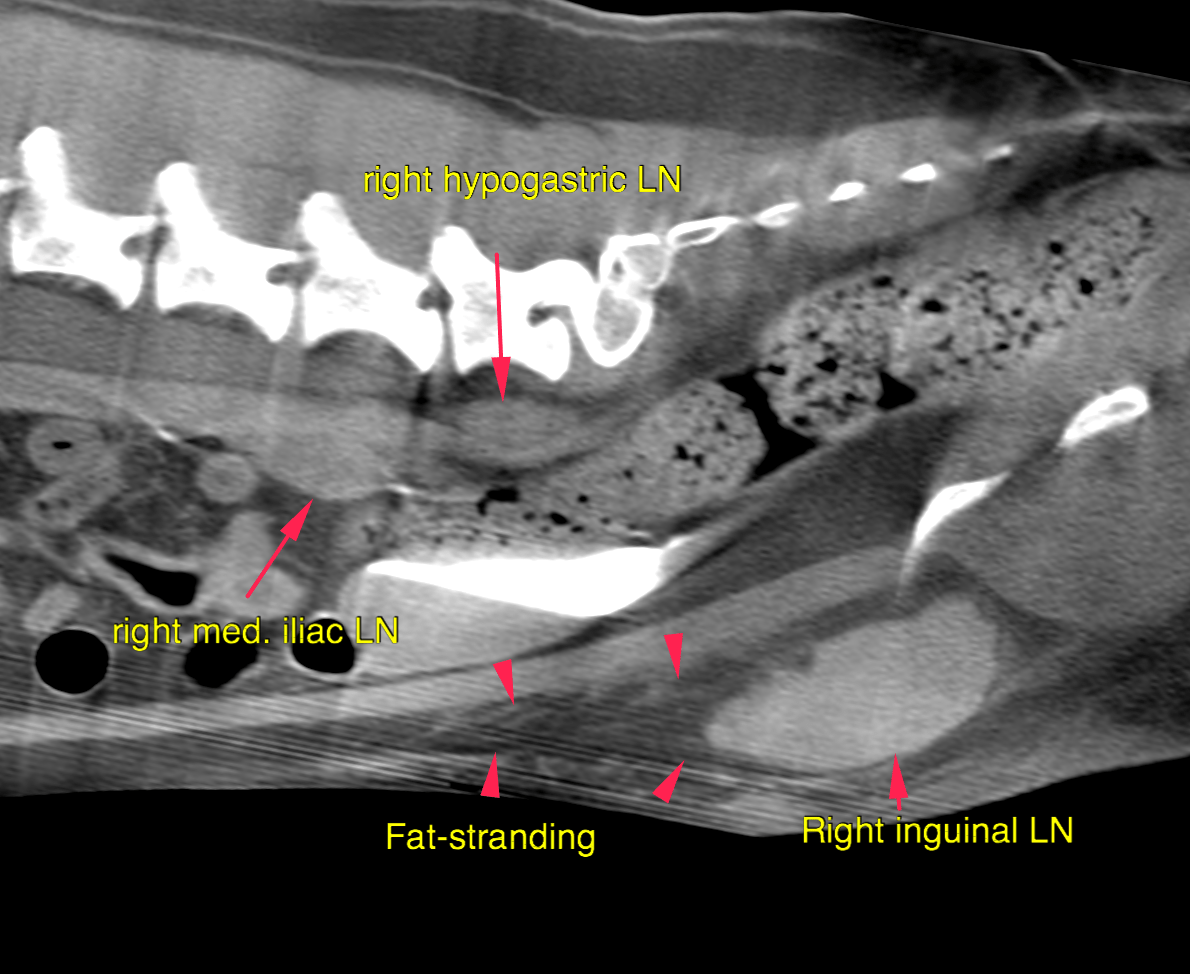

CT – Mast Cell with metastatic spread to right inguinal lymph nodes and tributaries in a 8 year ol FS German Short Haired Pointer

Neoplasia of the right inguinal lymph node meeting malignancy criteria with regional cellulitis

The right inguinal lymph node is severely enlarged at 3 x 2.2 x 6.1 cm with moderate peripheral fat-stranding, increased short-to-long-axis-ratio > 0.5 and irregular contrast enhancement. The right sided tributary lymph nodes (hypogastric, medial iliac and sacral) are markedly enlarged and rounded, short-to-long-axis-ratio > 0.5. The lymph nodes of the hypogastric area on the left side are prominent and rounded as well, short-to-long-axisratio > 0.5. The wall of the vagina/cervix presents moderate focal circumferential and transmural thickening at 1 cm cranial to the vaginal vestibulum.  The spleen is enlarged and rounded

In addition, lymphadenopathy of the hypogastric, medial iliac and sacral lymph-nodes

The findings are consistent with history of mast-cell tumor and metastatic spread to the

right inguinal lymph nodes and its tributaries including the contralateral side. The marked splenomegaly can be either caused by pooling of blood due to general